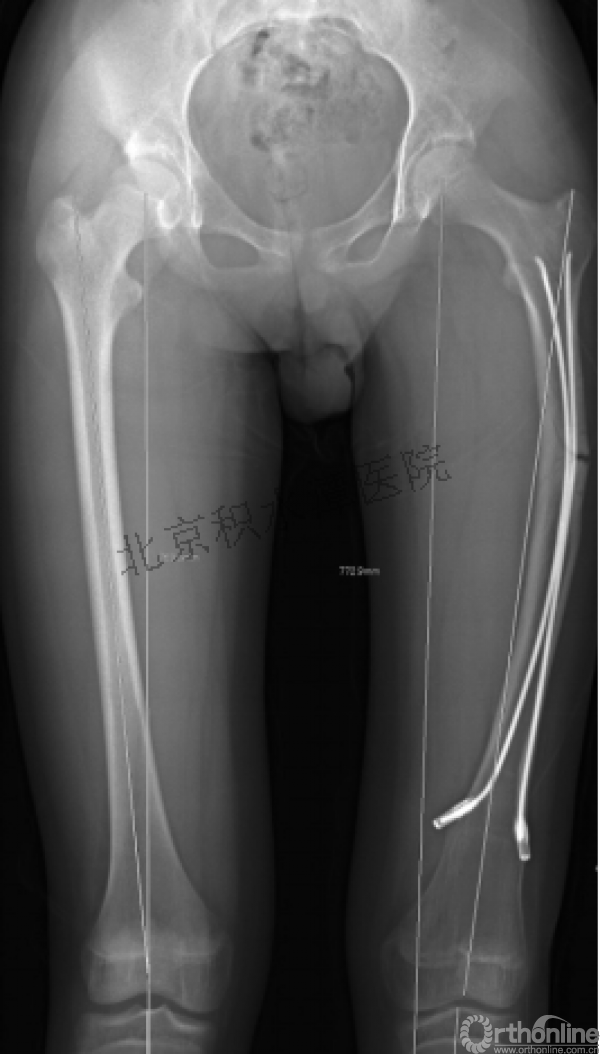

又过了4年!时间来到2015年

一年以后顺利愈合,实则危机四伏

数月后再骨折!牵引!

髋人字支具

外固定架术后一年

整整11年!是否治疗终结?